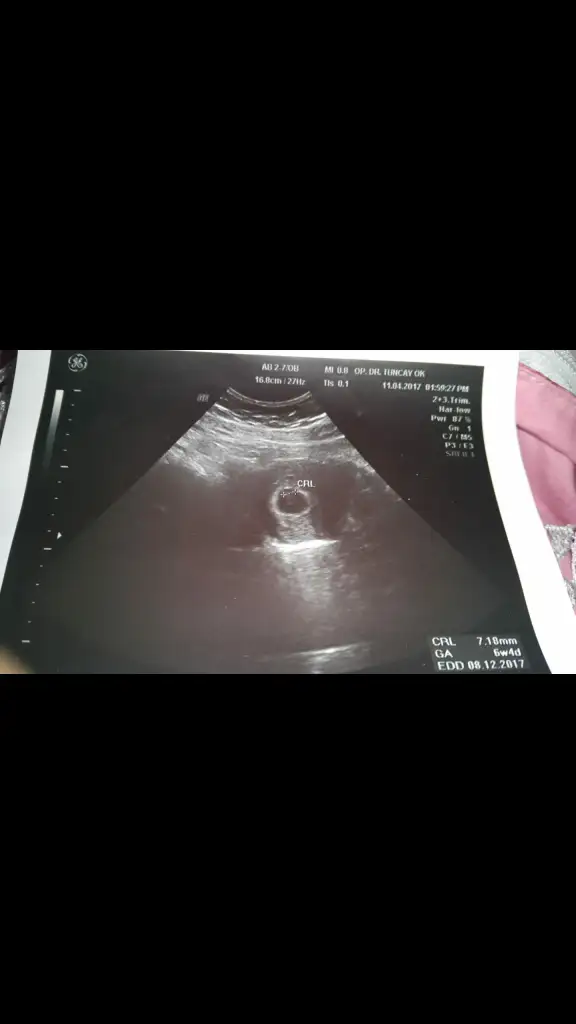

bu da 2.gebeliğim cinsiyet tahmini alabilir miyim ikisine de ikisi de 6 küsür haftalık usg ve karından

Benimkine de bakar mısınız 6+4